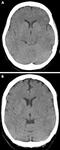

Two examples of early ischaemic changes on CT in sub-three hour ischaemic stroke. (A) Acute left middle cerebral artery (MCA) ischaemia with loss of insular ribbon, and hypodensity of tail of lentiform nucleus. (B) Similar changes in a different patient, with hypodensity of entire lentiform nucleus, some hemispheric sulcal effacement, and compression of lateral ventricle caused by hypodensity of caudate head

Muir KW et al. Neurology, Neurosurgery & Psychiatry 2005; 76: iii19-iii28; used with permission